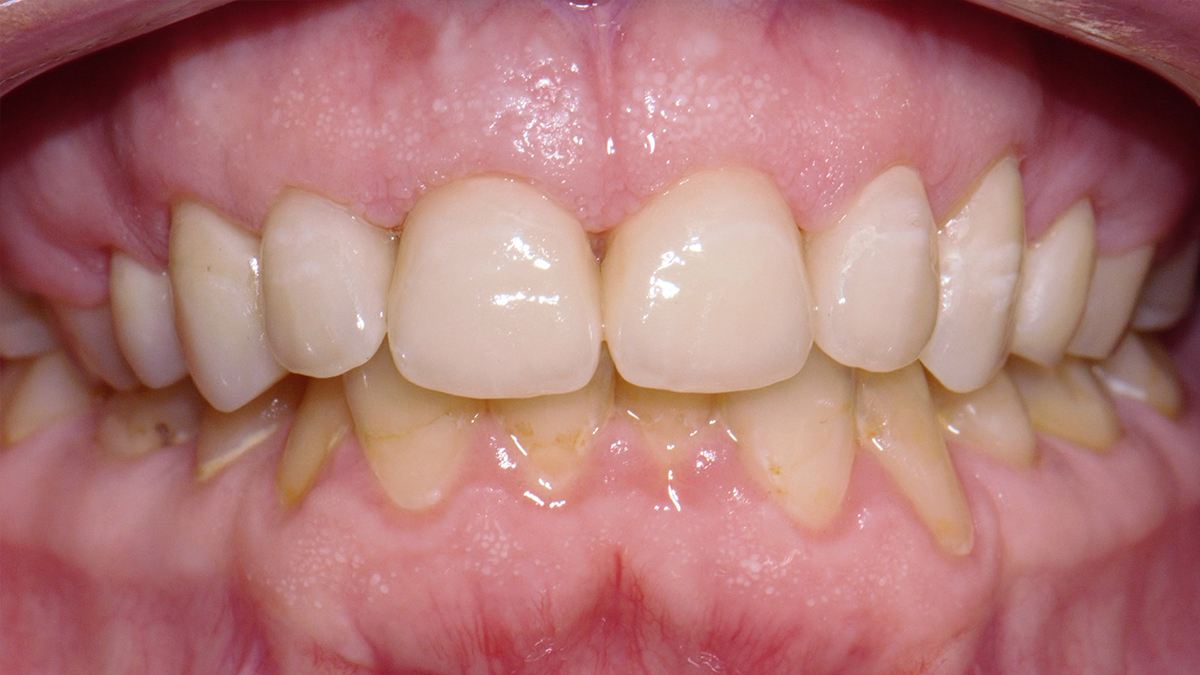

A tömőanyag tulajdonságaiból adódóan ma már, ha az üreg nem túl nagy, minden fogcsoport tömésére alkalmazható. Rágófogakban képes helyreállítani a funkciót, azaz egy erős, a rágóerőkkel szemben ellenálló tömés készíthető, frontfogakba (metszőfogak) pedig készülhet olyan esztétikus, észrevehetetlen tömés, mely kedvezően befolyásolhatja megjelenésünket, arckarakterünket.